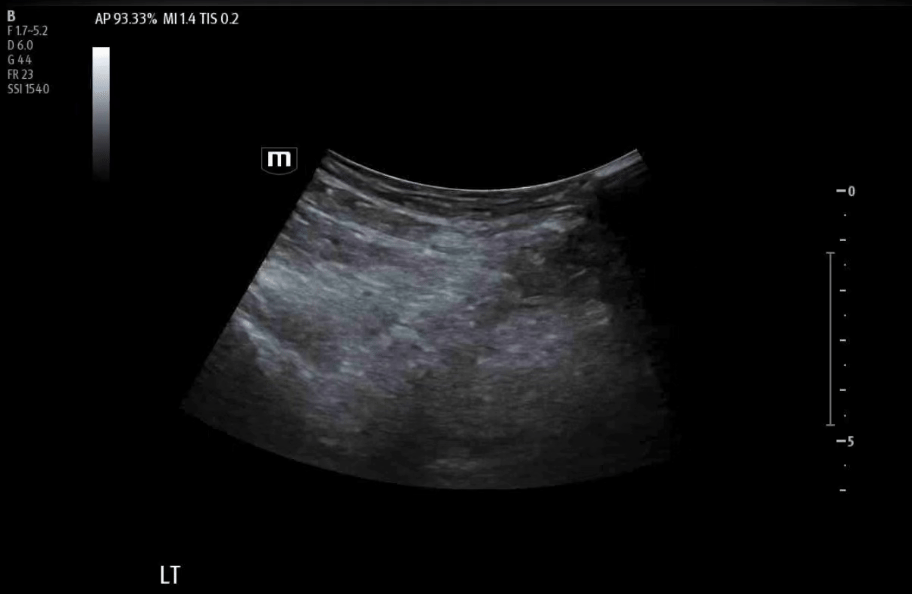

Color flow to confirm femoral neurovascular bundle.